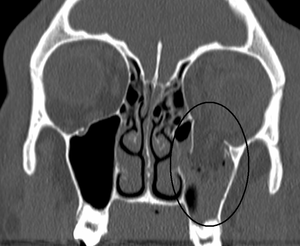

| An orbital blowout fracture of the floor of the left orbit. | |

An orbital blowout fracture is a traumatic deformity of the orbital floor or medial wall, typically resulting from impact of a blunt object larger than the orbital aperture, or eye socket. There are two broad categories of blowout fractures: open door, which are large, displaced and comminuted, and trapdoor, which are linear, hinged, and minimally displaced. They are characterized by double vision, sunken ocular globes, and loss of sensation of the cheek and upper gums due to infraorbital nerve injury.[1]

In pure orbital blowout fractures, the orbital rim (the most anterior bony margin of the orbit) is preserved, while with impure fractures, the orbital rim is also injured. With the trapdoor variant, there is a high frequency of extra-ocular muscle entrapment, despite minimal signs of external trauma, a phenomenon referred to as a 'white-eyed' orbital blowout fracture.[2] They can occur with other injuries such as transfacial Le Fort fractures or zygomaticomaxillary complex fractures. The most common causes are assault and motor vehicle accidents. In children, the trapdoor subtype are more common.[3] Reconstruction is usually performed with a titanium mesh or porous polyethylene through a transconjunctival or subciliary incision. More recently, there has been success with endoscopic, or minimally invasive, approaches.[4]

The most commonly fractured area in blowout fracture is the floor of orbit. Diagnosis is based on clinical and radiographic evidence. Periorbital bruising and subconjunctival hemorrhage are indirect signs of a possible fracture. On Water's view radiograph, polypoid mass can be observed hanging from the floor into the maxillary antrum, classically known as teardrop sign, as it usually is in shape of a teardrop. This polypoid mass consists of herniated orbital contents, periorbital fat and inferior rectus muscle. The affected sinus is partially opacified on radiograph. Air-fluid level in maxillary sinus may sometimes be seen due to presence of blood. CT scan can also show any soft tissue and bone involvement. Fracture of medial wall can produce subcutaneous emphysema, especially when blowing the nose or while sneezing. Lucency in orbits (on a radiograph) usually indicate orbital emphysema.